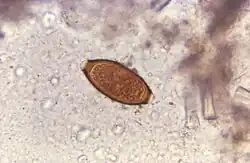

Adult worms are usually 3–5 centimetres (1.2–2.0 in) long, with females being larger than males as is typical of nematodes. The thin, clear majority of the body (the anterior, whip-like end) is the esophagus, and it is the end that the worm threads into the mucosa of the colon. The widened, pinkish-gray region of the body is the posterior, and it is the end that contains the parasite's intestines and reproductive organs. T. trichiura eggs are prolate spheroids, the shape of the balls used in Rugby and Gridiron football. They are about 50–54 μm (0.0020–0.0021 in) long and have polar plugs (also known as refractile prominences) at each end.

A stool ova and parasites exam reveals the presence of typical whipworm eggs. Typically, the Kato-Katz thick-smear technique is used for identification of the Trichuris trichiura eggs in the stool sample. Trichuria eggs often appear larger and more swollen on Kato-Katz preparation compared to when using other techniques.[19]

Trichuriasis can be diagnosed when T. trichiura eggs are detected in stool examination. Eggs will appear barrel-shaped and unembryonated, having bipolar plugs and a smooth shell.[21] Rectal prolapse can be diagnosed easily using defecating proctogram and is one of many methods for imaging the parasitic infection. Sigmoidoscopies show characteristic white bodies of adult worms hanging from inflamed mucosa ("coconut cake rectum").[22]